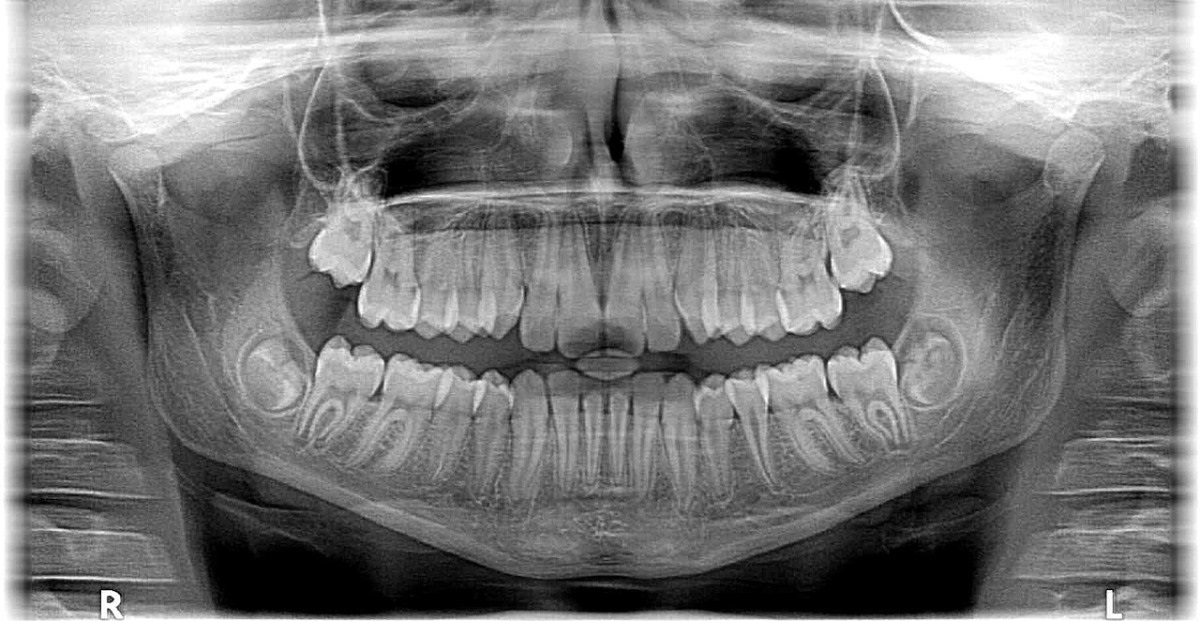

Oral and maxillofacial radiology is an evolving field with many new technologies and applications. Artificial intelligence (AI) should play an especially important role in this field in the coming future, as many original research reports have been published to describe its various applications, such as tooth identification; disease diagnosis; segmentation of tooth, anatomical structures, odontogenic and non-odontogenic lesions in the jaws; and surgical planning. Meanwhile, 3D imaging and modalities involving non-ionizing radiation (e.g., MRI and ultrasound) continue to develop and take on heavier roles in clinical practice than before. This Special Issue aims to collate high-quality research papers (original research, review, bibliometrics, meta-analysis, etc.) that describe recent applications of oral and maxillofacial radiology, in the overlapping fields of (but not limited to):